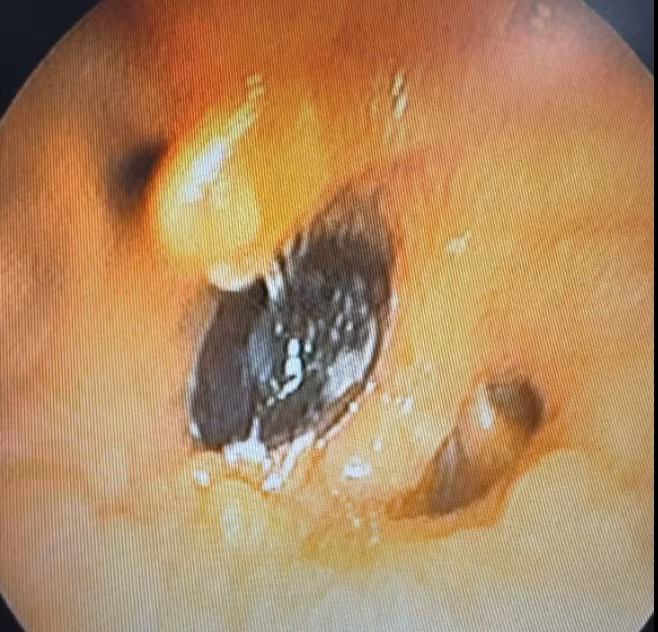

Kết quả chụp cắt lớp vi tính ghi nhận hình ảnh bất thường tại phế quản phải. Nội soi phế quản sau đó phát hiện một dị vật là hạt hồng xiêm kích thước hơn 2cm nằm ở phế quản thùy dưới phải, gây chít hẹp lòng phế quản, kèm tổ chức hạt và viêm phổi hậu tắc.

hat-1.jpg

Hạt hồng xiêm trong đường thở bệnh nhân trên phim chụp - Ảnh BVCC